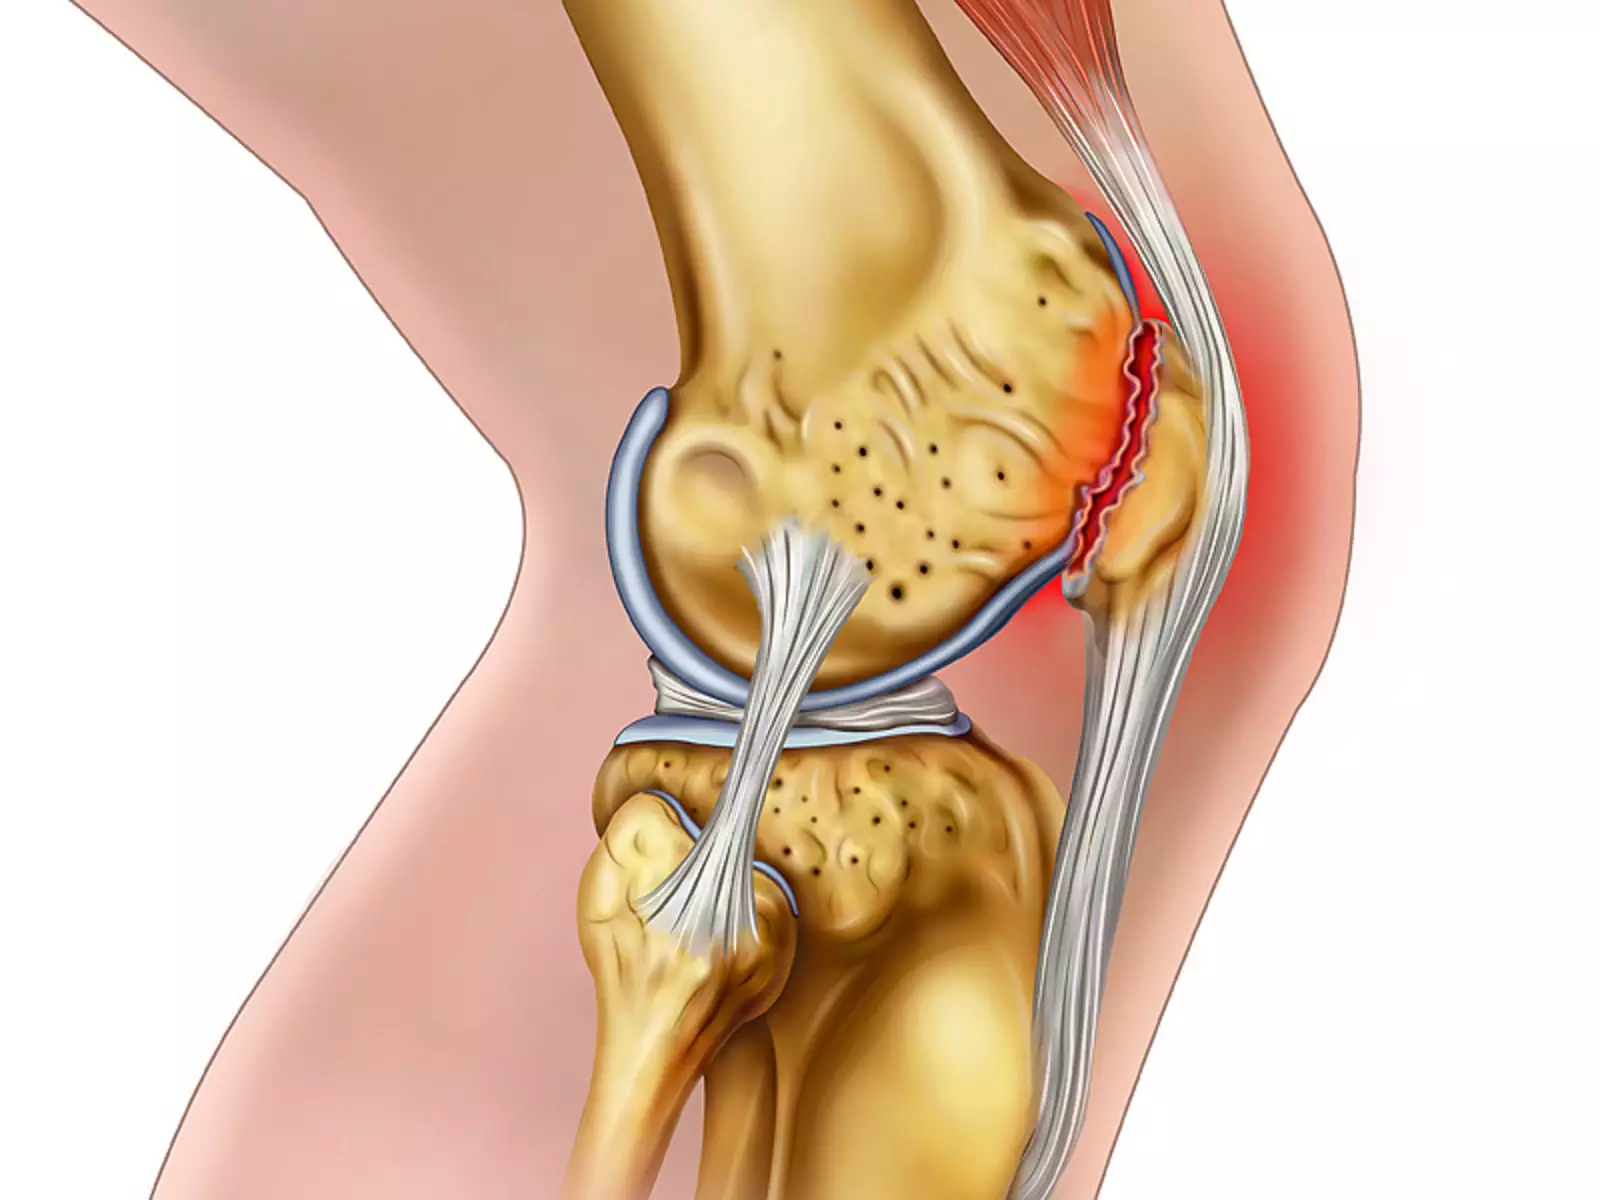

Анатомия коленного сустава: изучение анзерита и его влияния